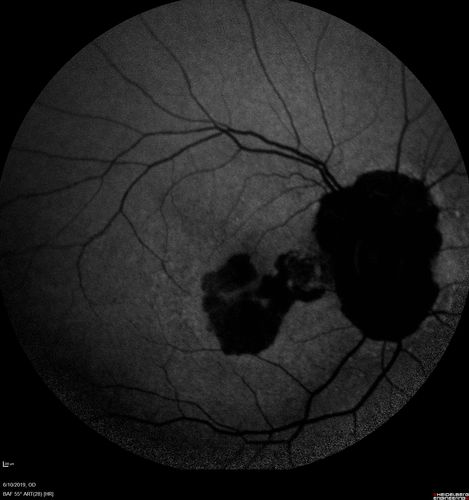

Melanosis Oculi and Choroidal Melanoma

88 year old female with 2.5 mm elevated choroidal melanoma and melanosis oculi.  She also has geographic atrophy from AMD.  The right eye is the better eye with 20/40 vision.  After observation with growth, brachytherapy was done.